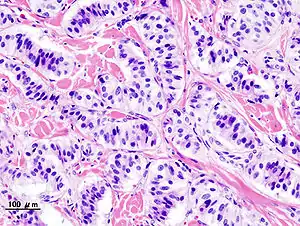

![]() Мікрофотознімок інсуліноми Мікрофотознімок інсуліноми | |